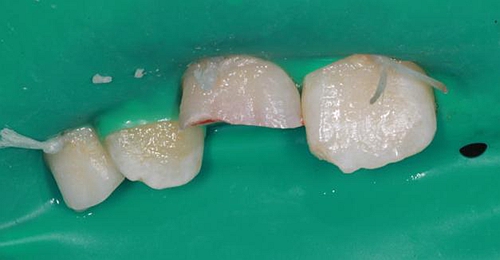

因周末處理該患者,無法領(lǐng)取纖維樁,于是將切斷的碎片復位后,從碎片舌側(cè)面制備一隧道直至根管口深處,(想法是注入流體樹脂形成一個樹脂樁加強固位),然后同上病例中所用方法,粘結(jié)固定斷端。如下圖:

第二日復查,給予樹脂恢復A2A1B1切斷缺損。術(shù)后如下圖: